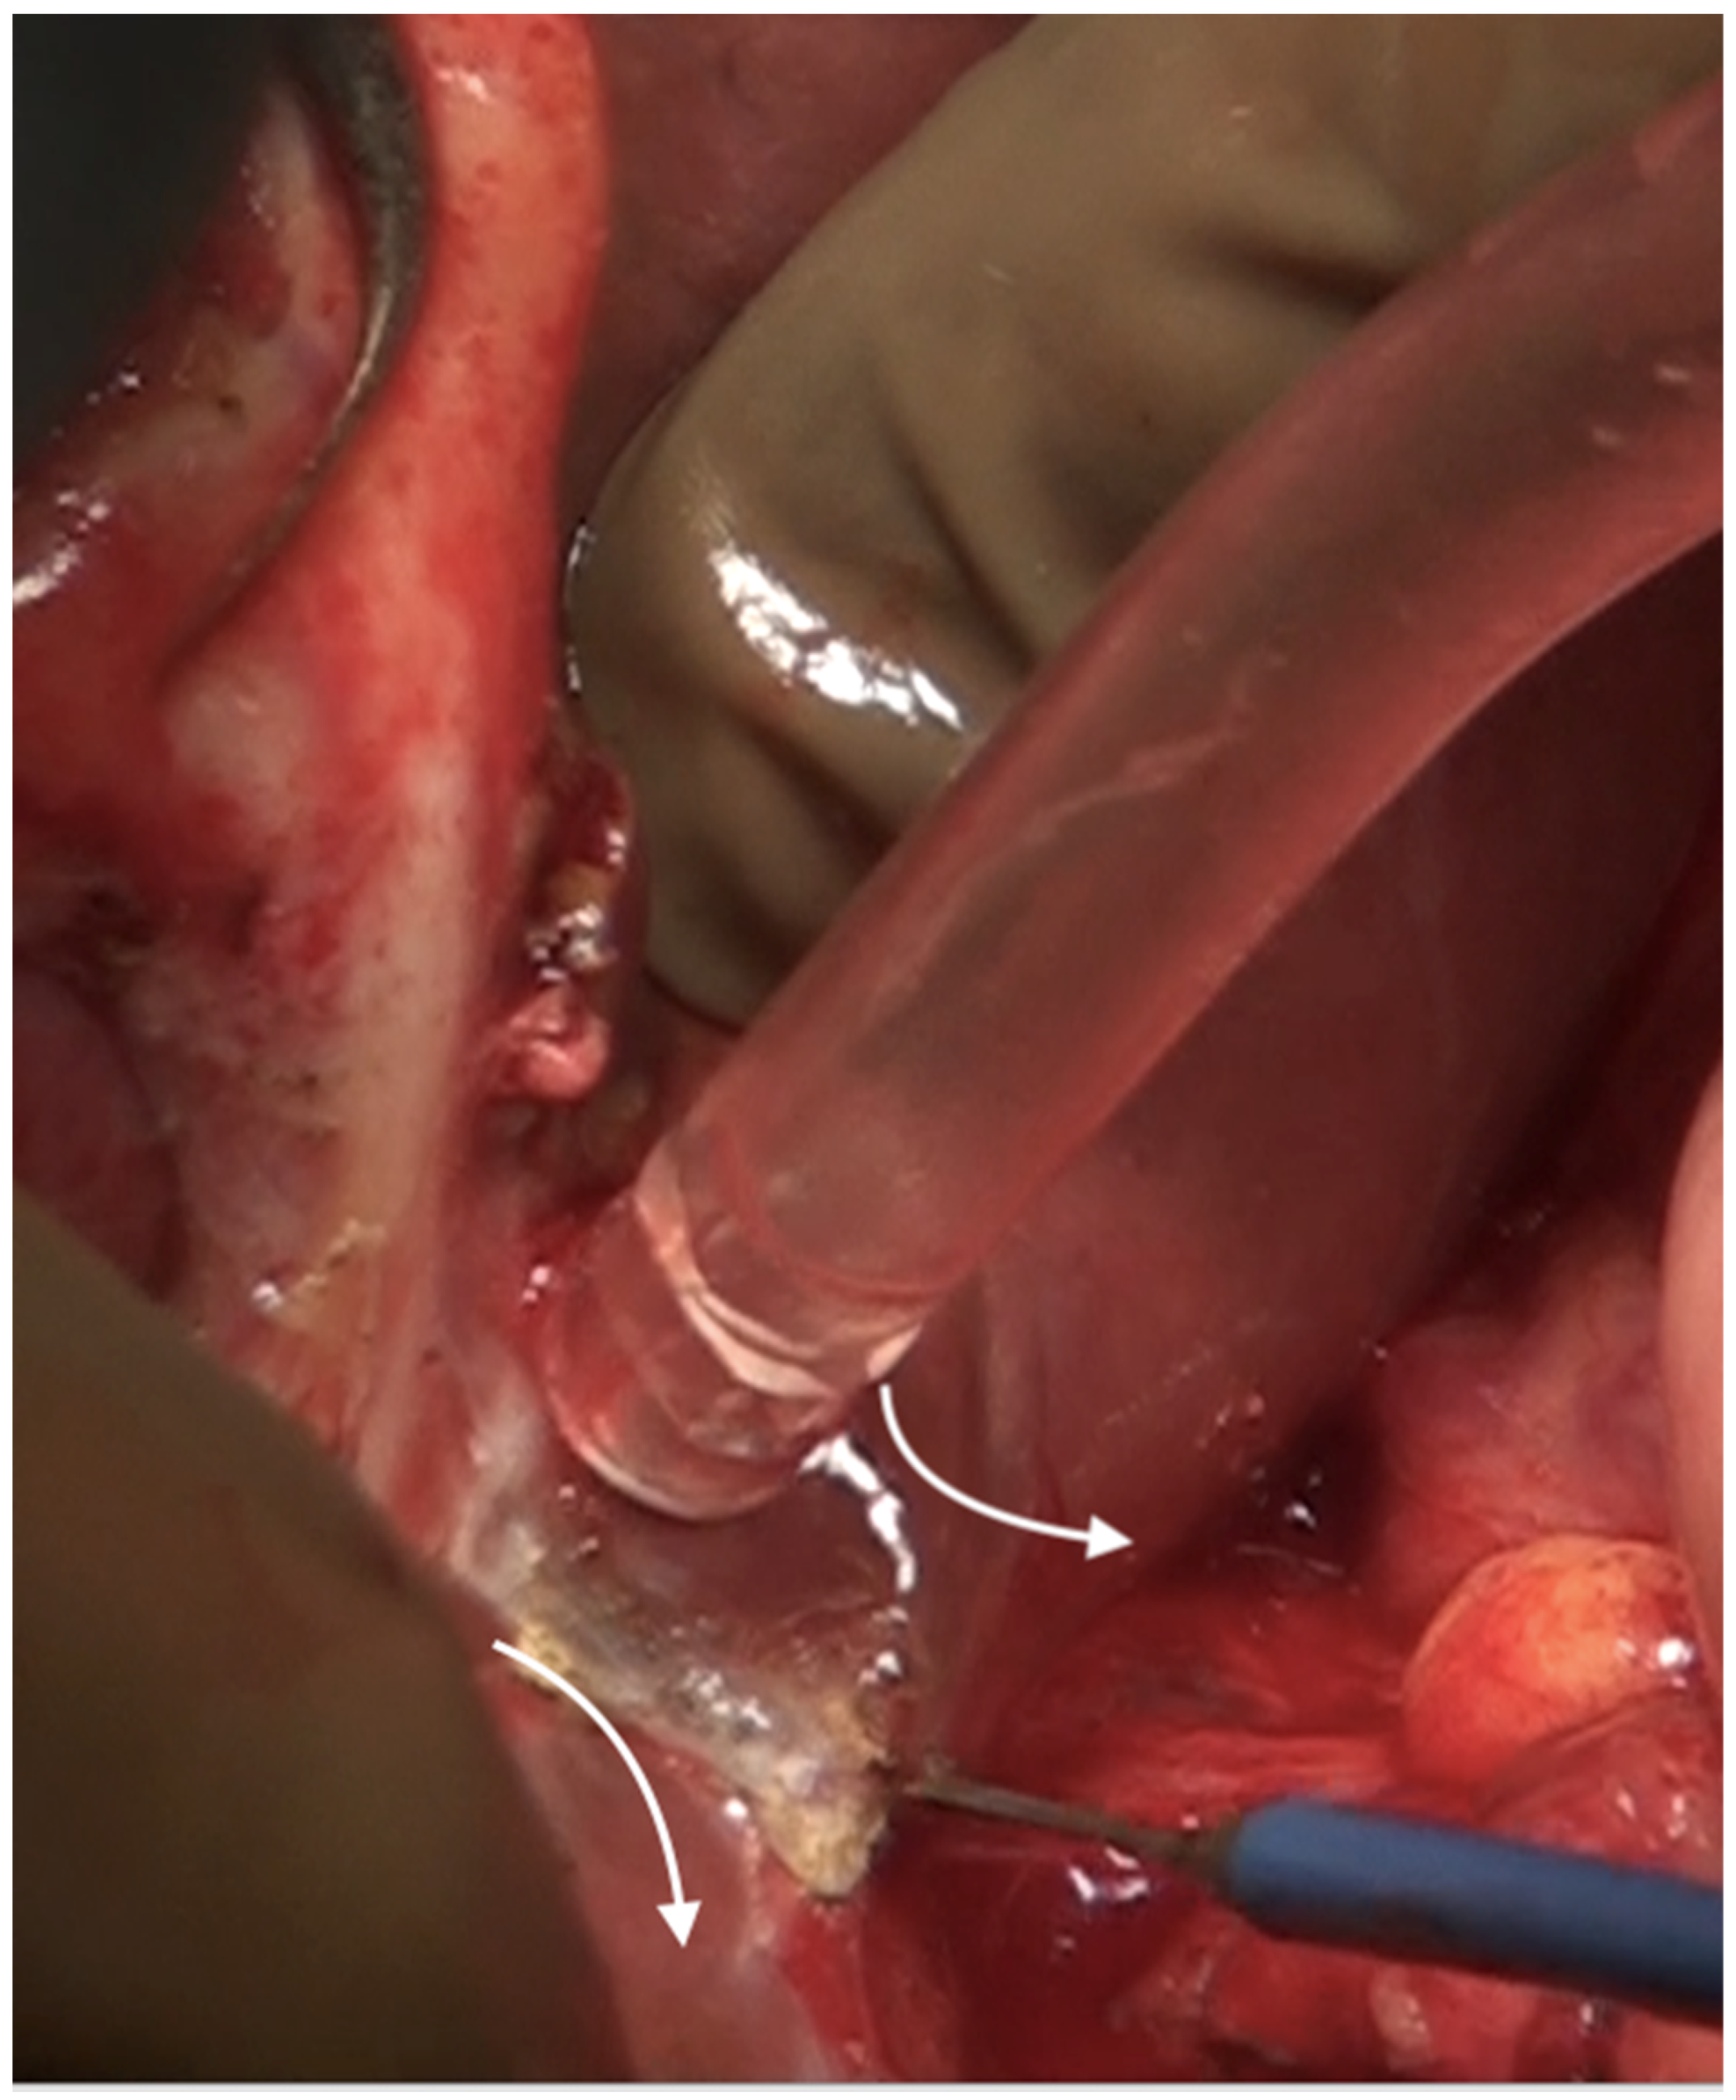

6.6. Foramen of Winslow and the Posterior Layer of the Hepatoduodenal Ligament

The posterior layer of the hepatoduodenal ligament covering the portal structures and the foramen of Winslow are two other sites of disease in the upper abdomen, especially in patients with extensive disease (Figure 24). The posterior layer of the hepatoduodenal ligament forms the anterior boundary of the foramen of Winslow, which is also bounded by the peritoneum covering the IVC posteriorly, the junction of the right and left caudate lobes of the liver superiorly, and by the peritoneum covering the first portion of the duodenum inferiorly [67]. Tumor nodules in this region may not be visible unless looked for. Whereas tumor on the IVC can be easily visualized, the posterior part of the porta should be palpated to determine the presence of disease. Sugarbaker et al. have also described this site as a potential for incomplete cytoreduction in patients with mucinous appendiceal neoplasms [69].

Figure 24.

Foramen of Winslow and the posterior layer of the hepatoduodenal ligament after removal of the anterior layer and the gall bladder.

When there are few nodules, the peritoneum can be removed from both the anterior surface of the IVC and the posterior surface of the porta using blunt or sharp dissection or a combination of both [55]. The peritoneum is divided at its attachment to the liver, safeguarding the portal structures. When there is a more bulky disease, Kocher’s maneuver (mobilization of the duodenum and the pancreas) can be used to provide better exposure to the Foramen of Winslow, as described by Sugarbaker et al. [67]. This procedure opens up the retroperitoneal space with the risk of retroperitoneal tumor implantation. Thus, it should be undertaken only when a complete cytoreduction has been obtained in all other regions. Rare complications that could arise are acute pancreatitis due to rotation of the pancreatic head and capsular injury [67].